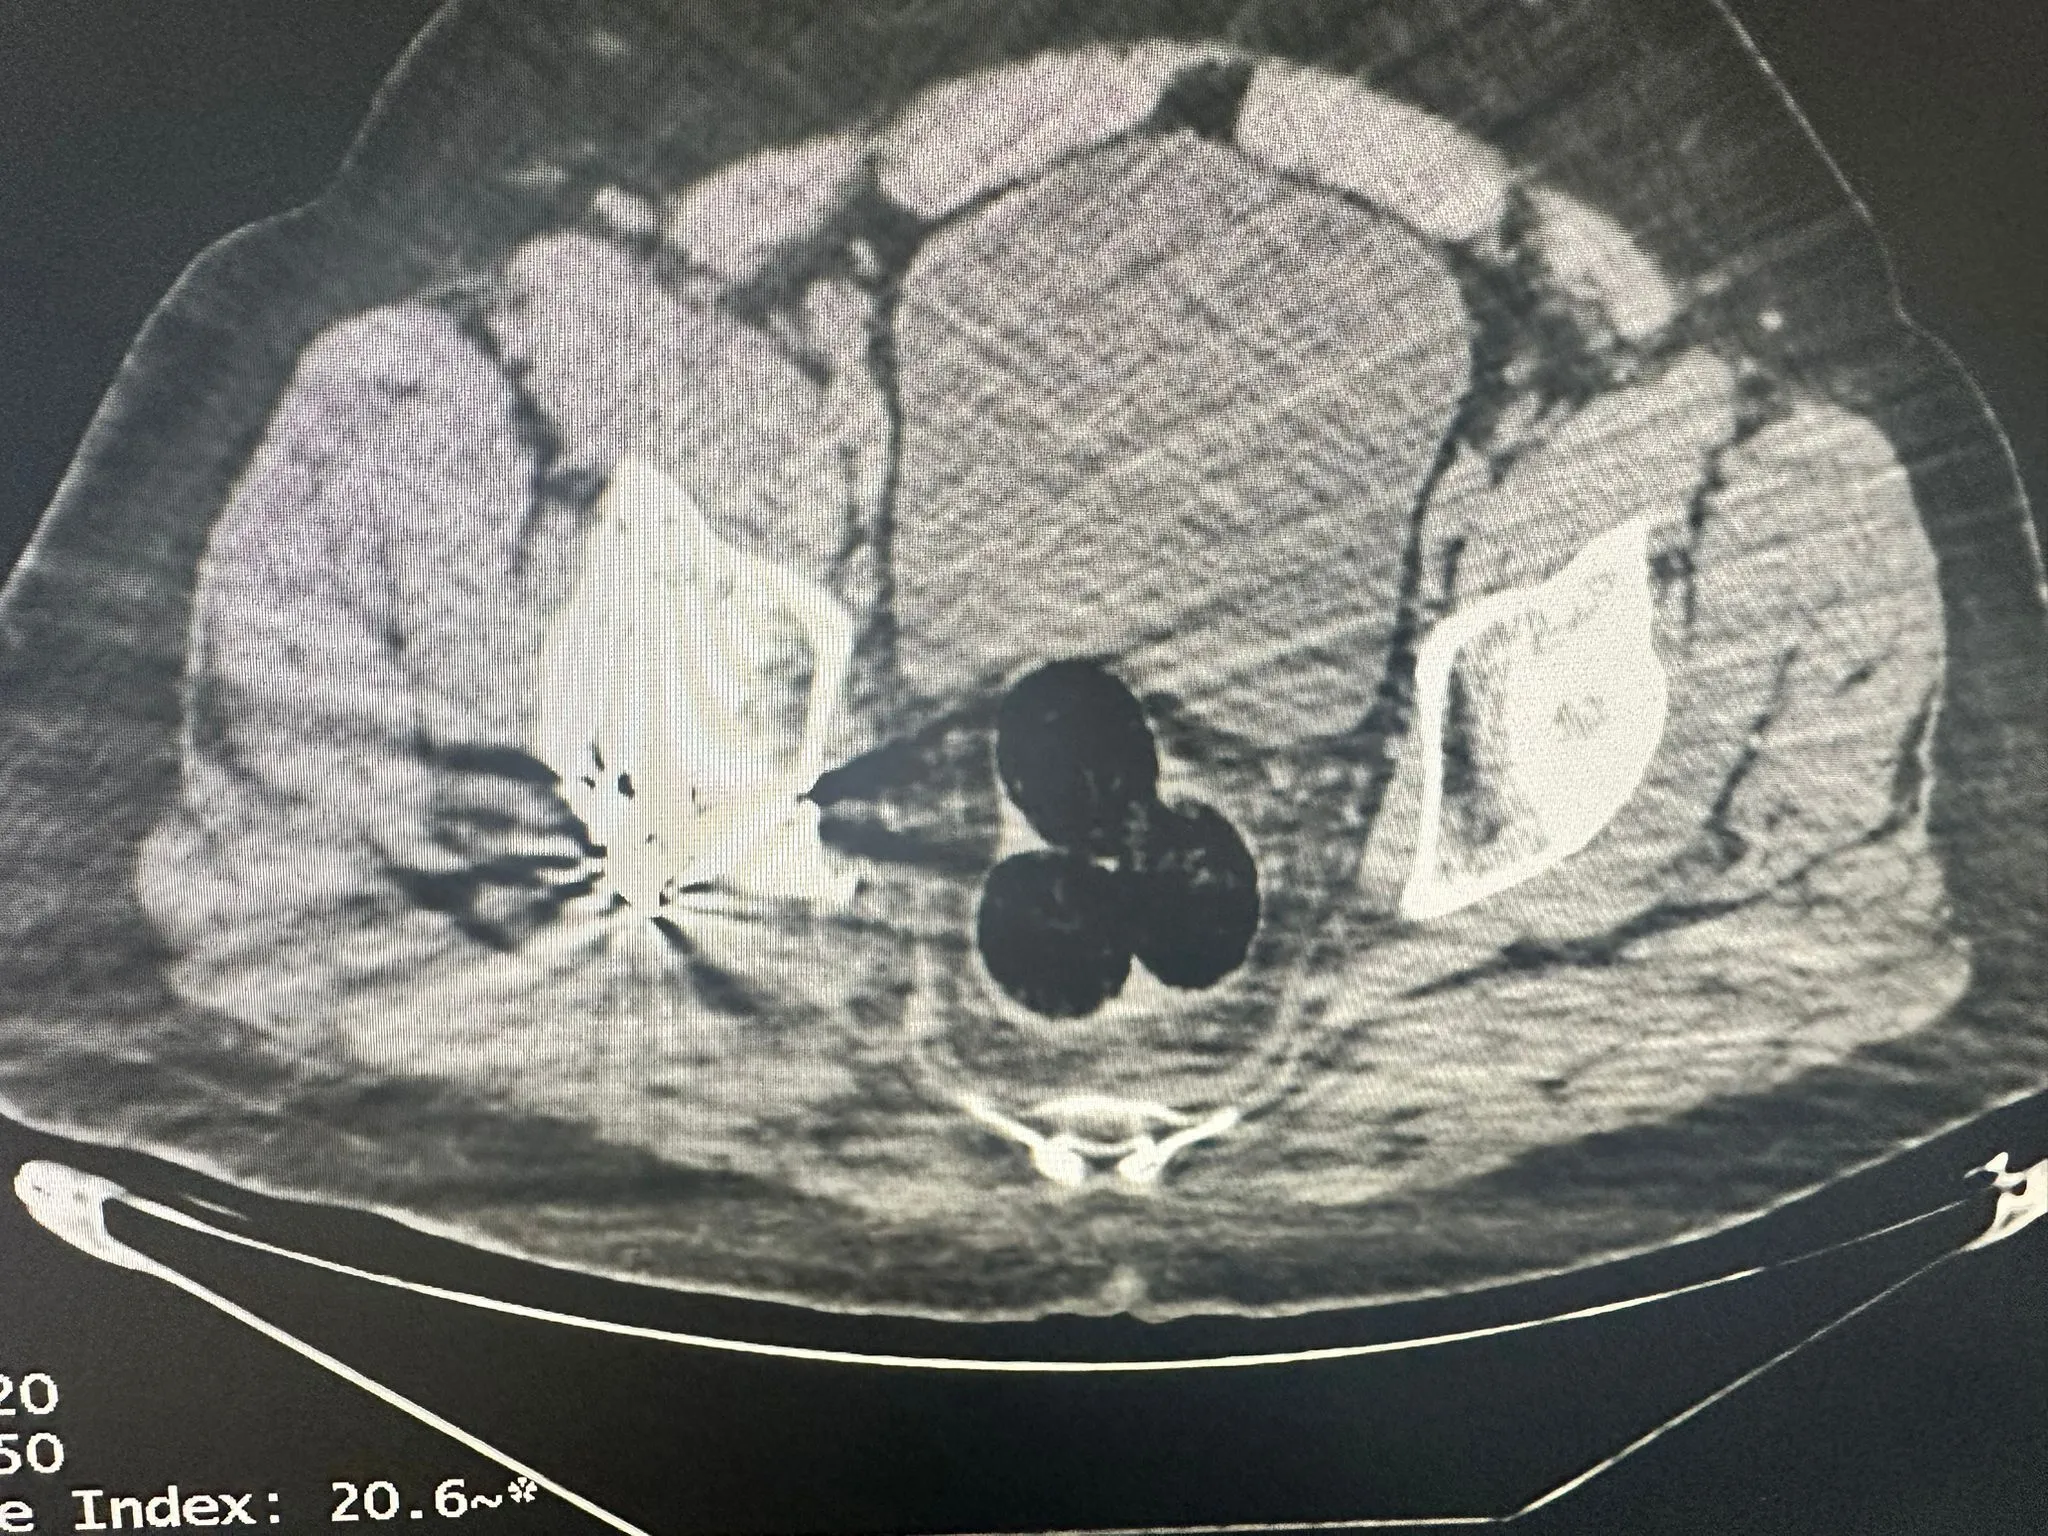

İran’dan ülkeye giriş yapan ve uyuşturucu maddeleri vücut boşluklarında (Makatında) taşıdığı belirlenen yabancı uyruklu bir şahıs takibe alındı ve il merkezinde yakalandı. Şahsın radyolojik görüntüleme yöntemiyle yapılan iç beden muayenesinde, vücudunda 3 parça halinde yabancı cisim olduğu tespit edildi. Bu cisimler çıkarılarak el konuldu.